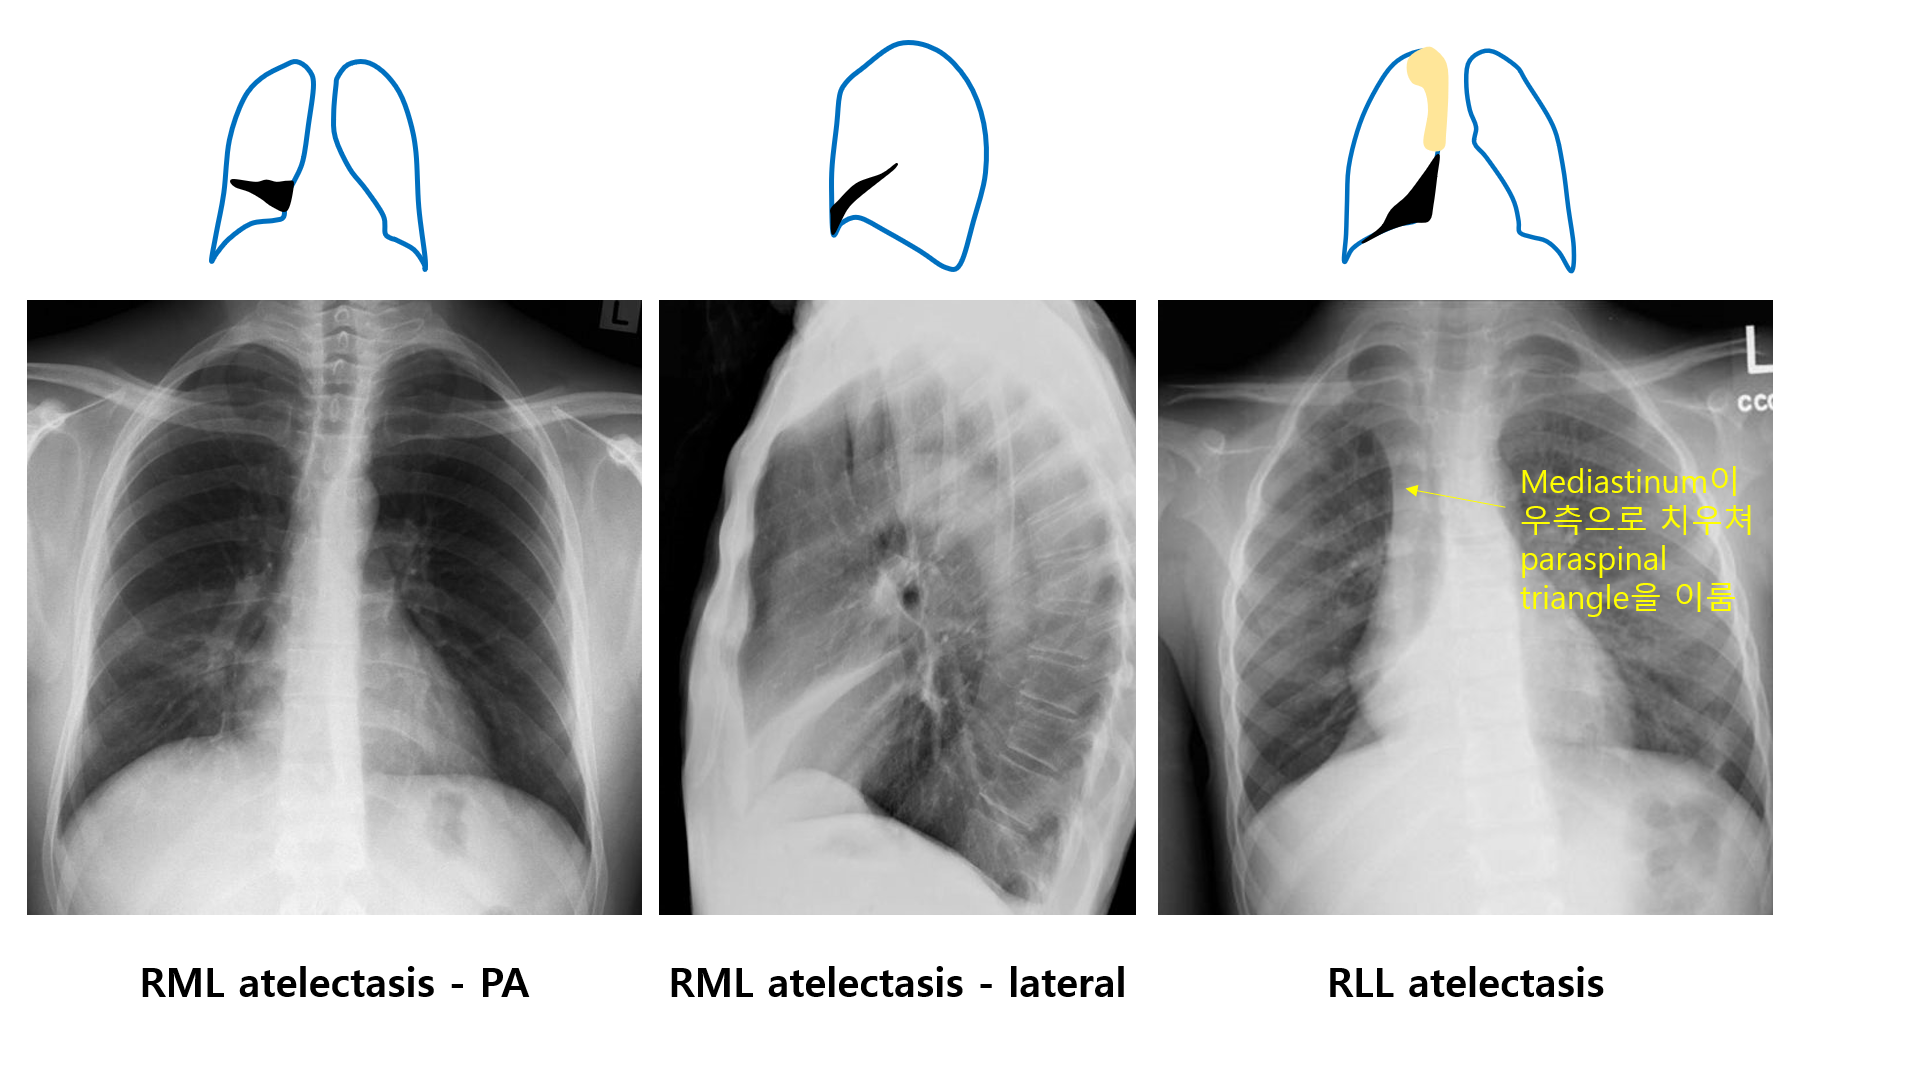

4) 각 lobe의 CXR 소견

(2) RML 무기폐

① PA/AP view에서는 잘 보이지 않음 (매우 옅은 쐐기 모양으로 보일 수도 있음)

② Lateral view에서 쐐기 형태로 잘 보임

(3) RLL 무기폐

① 우하폐야 medial 쪽에 삼각형 모양의 opacity

② Upper mediastinum의 구조물이 우측으로 당겨져 보임